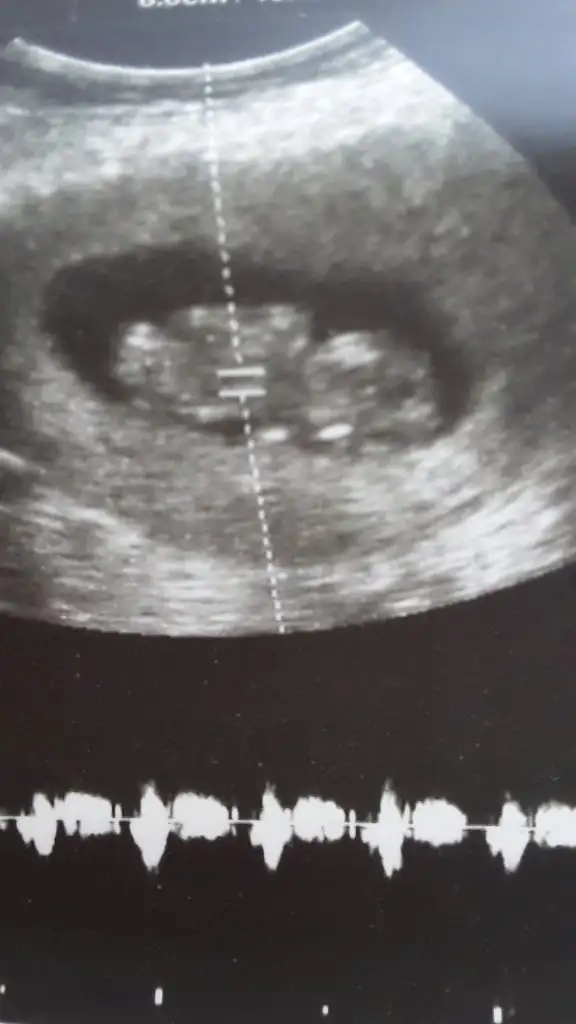

11 12 13 hafta usg olmalı burada 14 haftada nub oluşmuş oluyor sanki emin değilim erkek gibi gibi istediğim usg leride paylaşın14 haftalık tahmin edermisiniz

10+5 burda Pazartesi kontrolüm var 12+1 olucaz inşallah atarım ozamanUsg net değil kaç hafta usg 12 13 de paylaşırsınız emin değilim sanki kız

Net değil 12 13 haftada paylaşın sanki eminde değilim erkek gibi gibi